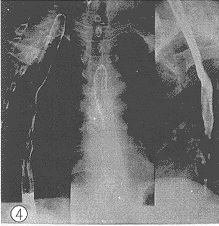

图3 食管中段癌示龛影及破坏

图4 放射治疗第14d后炳灶被显著修复

2.1 X线影像比较:每例患者在术前加速放射治疗结束后第2d及第14d分别两次摄食管钡餐造影片。由放射科、放射治疗科、胸外科3名副主任医师以上的人员读片,读片前用胶布粘住每例患者的摄片的日期,再进行“多盲法”对比观察、记录。评判标准按1981年第三届全国放射学术会议(郑州)治疗组通过的食管癌放射治疗后X线诊断标准分为4级。Ⅰ级:病变完全消失,食管壁软而光滑,蠕动及扩张良好,粘膜纹理清楚可见(图1、 2);Ⅱ级:病变基本消失,食管壁规则,钡剂能顺利通过,但管壁仍僵直或狭窄,蠕动未恢复,粘膜仍增粗(图3、 4);Ⅲ级:病变明显好转,食管病灶退缩一半以上,没有明显扭曲、成角以及突出腔外的溃疡,稠的钡剂能通过(图5、 6);Ⅳ级:病变残留或恶化,病灶消退不到一半或成角,扭曲明显或有突出腔外的溃疡,钡剂通过极差(图7、 8)。118例术前加速放射治疗后不同时间的X线影像变化结果中,从Ⅲ、Ⅳ级病例上升为Ⅱ、Ⅲ级者最多,分别达 37.8%(17/45)和43.8%(7/16);但未发现越级上升和降级病例。